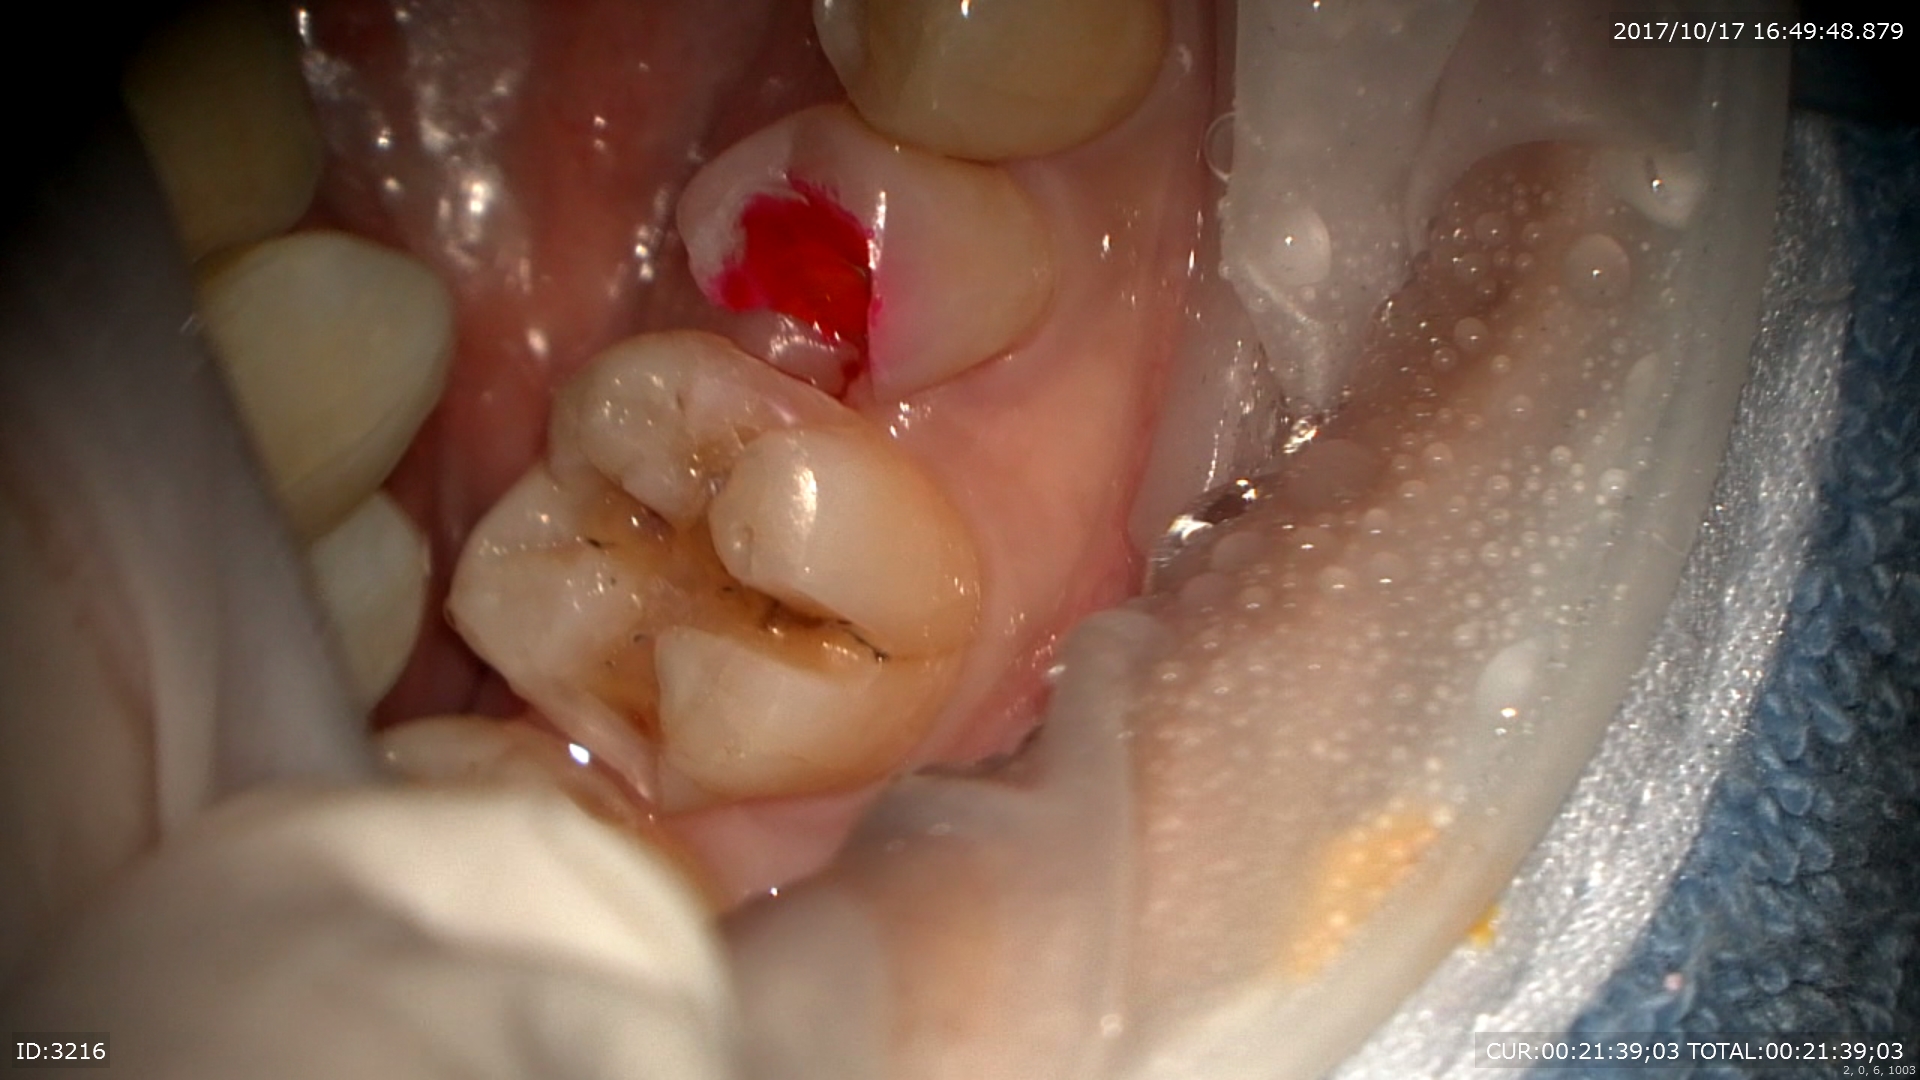

むし歯が取りきれました。直ぐ神経です!!守らなきゃ

神経保護を行いました。